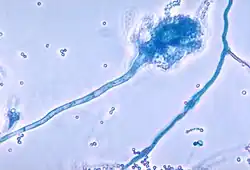

In people with predisposing lung diseases—such as persistent asthma or cystic fibrosis (or rarer diseases such as chronic granulomatous disease or Hyper-IgE syndrome)—several factors lead to an increased risk of ABPA.[11] These include immune factors (such as atopy or immunogenic HLA-restricted phenotypes),[12][13] as well as genetic factors (such as CFTR gene mutations in both asthmatics and cystic fibrosis patients and a ZNF77 mutation resulting in a premature stop codon in asthmatics and ABPA patients).[14][10][15] By allowing Aspergillus spores to persist in pulmonary tissues, it permits successful germination which leads to hyphae growing in mucus plugs.

Aspergillus also uses several factors to continue evading host responses, notably the use of proteolytic enzymes that interrupt IgG antibodies aimed towards it. Another important feature is its ability to interact and integrate with epithelial surfaces, which results in massive pro-inflammatory counter-response by the immune system involving IL-6, IL-8 and MCP-1 (a CCL2 receptor ligand). Proteases released by both the fungus and neutrophils induce further injury to the respiratory epithelium, leading to initiation of repair mechanisms (such as an influx of serum and extracellular matrix (ECM) proteins) at the site of infection. Aspergillus spores and hyphae can interact with ECM proteins, and it is hypothesised that this process facilitates the binding of spores to damaged respiratory sites.[10][21]